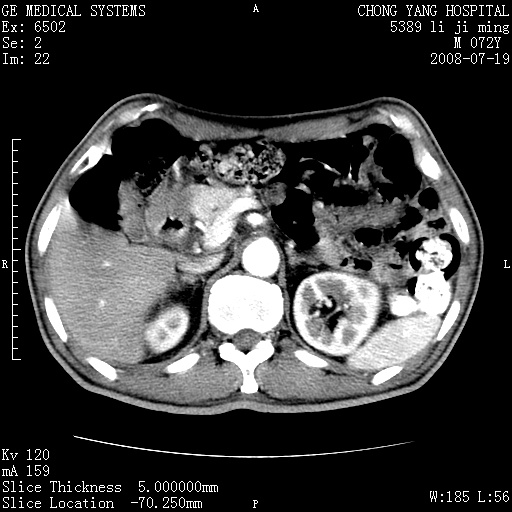

以下是引用zjzjr在2008-7-19 20:57:00的发言:[br]胰头增大,边缘模糊,周围可见渗出影,右侧肾前筋膜增厚.支持胰腺炎.

以下是引用yangyudong333在2008-7-20 6:56:00的发言:[br]胰腺增大尤以胰头明显,边缘模糊,周围可见渗出影,右侧肾前筋膜增厚,肠管於涨.支持胰腺炎

以下是引用不学无术在2008-7-19 23:15:00的发言:[br]胰腺增大尤以胰头明显,边缘模糊,周围可见渗出影,右侧肾前筋膜增厚,肠管於涨.支持胰腺炎